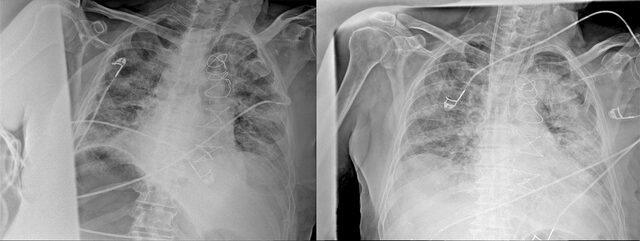

Normal akciğer görüntüleri ile koronavirüs hastalarının akciğer görüntüleri arasında ciddi farklar bulunduğunu belirten Karalezli, şu bilgileri verdi:

"İnsanların aradaki farkları anlamaları için her iki akciğer görüntülerine de yer verdim. Görüntülerdeki beyazlıklar akciğerdeki tutulumu gösteren görüntüler ne yazık ki. Bu hastalar yoğun bakım hastaları. Filmler birbirine az çok benzeyen şekilde. Altta yatan hastalığı olanlarda ise daha kötü seyrediyor."

Kliniğe yeni başvuran bir hastanın, 5 Ağustos'ta çekilen tomografi görüntülerindeki tipik koronavirüs görüntülerinin olduğunu ifade eden Karalezli, hastanın bir hafta içerisindeki tomografi görüntüsünde ciddi değişiklik olduğunu ve enfeksiyonun çok arttığını söyledi.